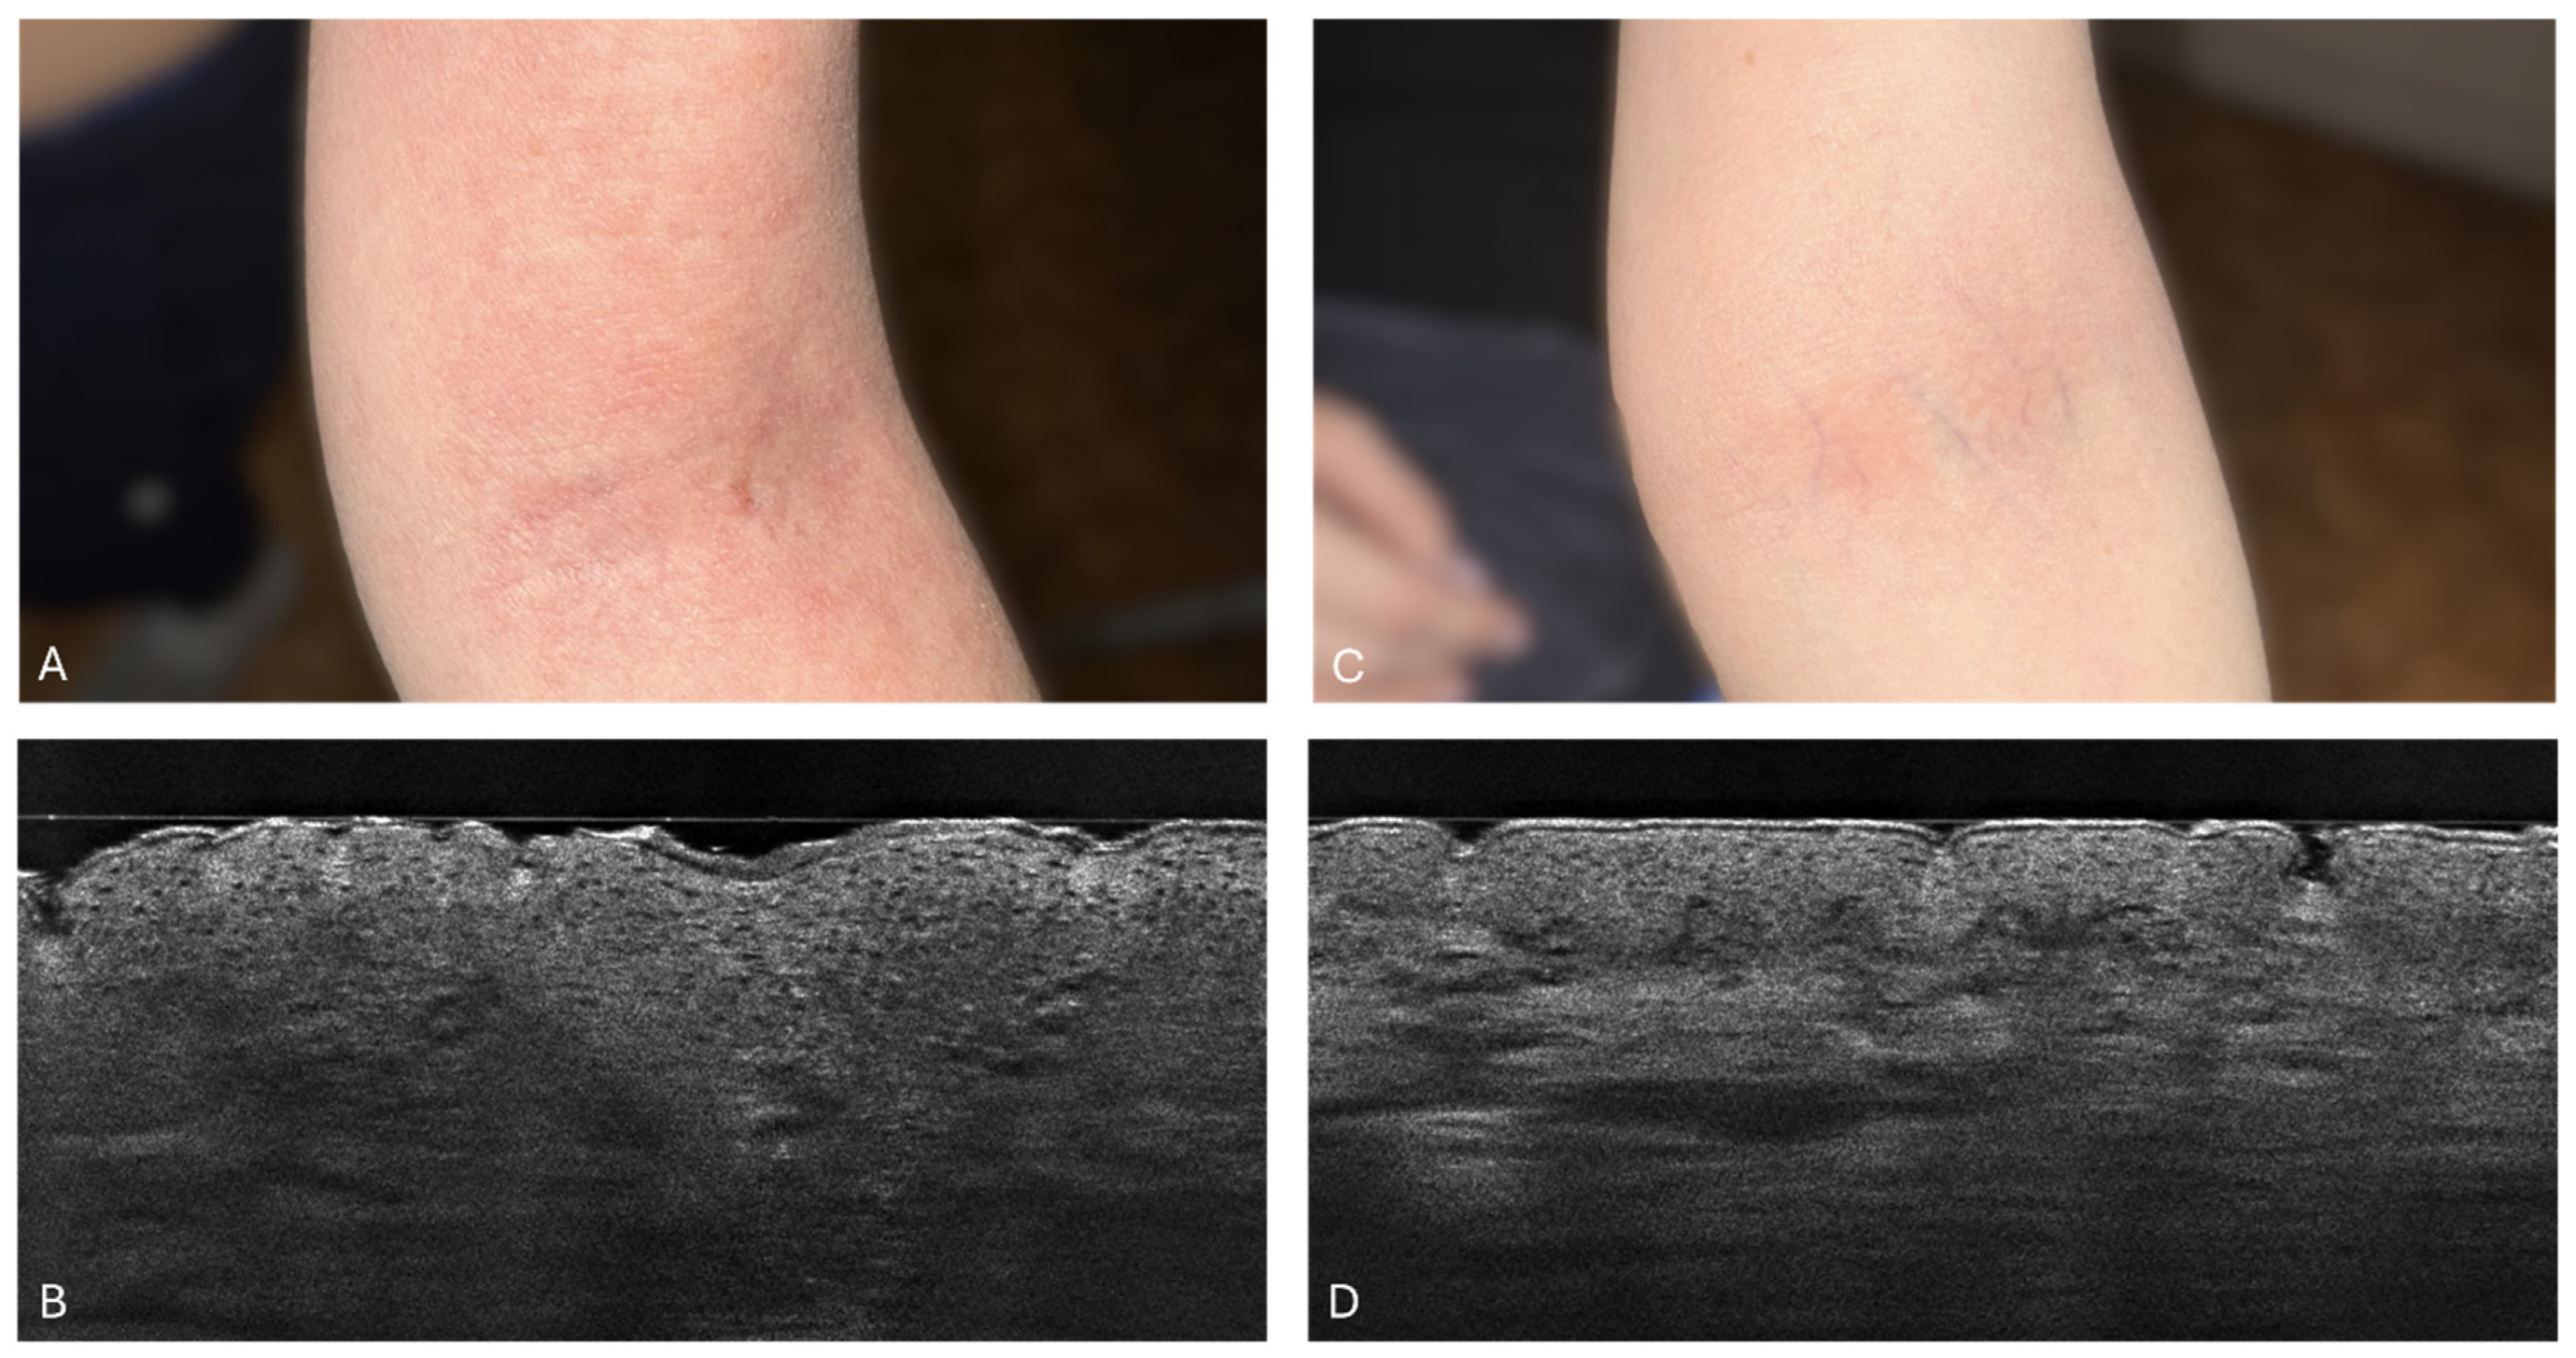

3.1. Atopic Dermatitis in LC-OCT

3.2. Stratum Corneum Thickness

3.3. Stratum Corneum Disturbances

3.4. The Epidermal Thickness